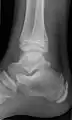

Ankle

Accessory bones at the ankle mainly include:

- Os subtibiale, with a prevalence of approximately 1%.[14] It is a secondary ossification center of the distal tibia that appears during the first year of life, and which in most people fuses with the shaft at approximately 15 years in females and approximately 17 years in males.[14]

- Os subfibulare, with a prevalence of approximately 0.2%.[15]

Os trigonum (further described below) may also be seen on an ankle X-ray.